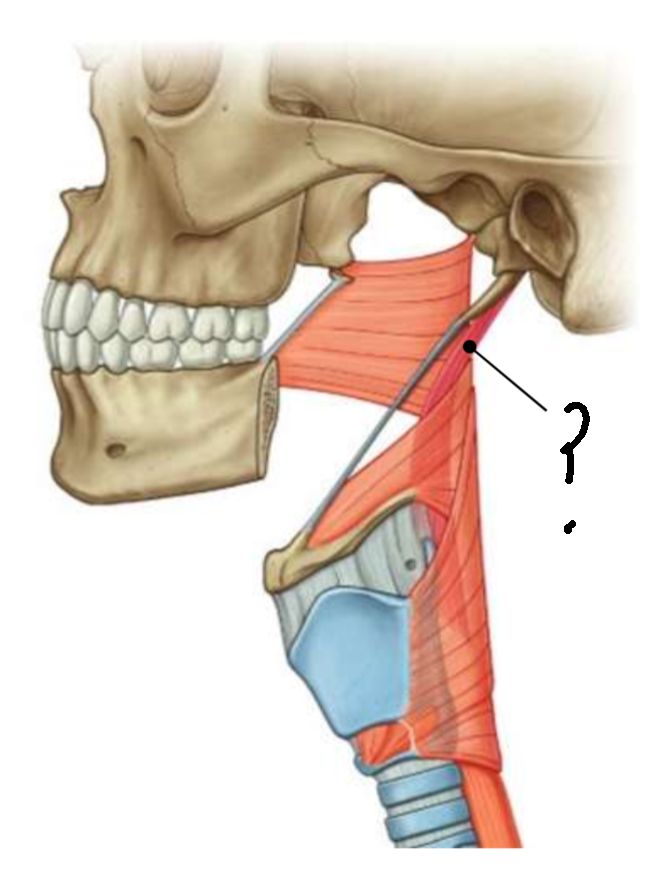

What muscle is this?

superior constrictor

What is the upper border of this muscle?

palatopharyngeal sphincter

What is 1?

pterygomandibular raphe

What is 2?

stylohyoid ligament

What are the attachments of this muscle?

pterygoid hamulus, pterygomandibular raphe, posterior end of mylohyoid line → pharyngeal raphe